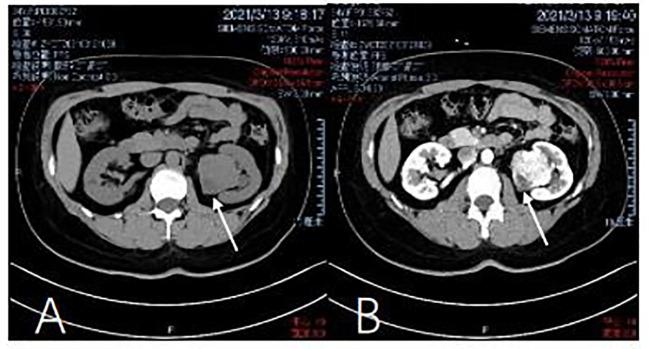

We report a typical case of SFT of the kidney. A 34-year-old woman presented to the urinary surgery department after physical examinations were suggestive of a urologic neoplasm. Further relevant imaging investigations suggested a renal tumor with benign behaviors. The patient was diagnosed with a kidney tumor suspected to be SFT and underwent laparoscopic radical left nephrectomy. Postoperative pathological immunohistochemical tests showed positivity for Signal Transducer and Activator of Transcription 6(STAT6), CD-34, CD-99, and Bcl-2, thus confirming the diagnosis of SFT. Combined with the results of genetic testing of the patient, the tumor was indicated to carry NGFI-A-Binding protein 2(NAB2): exon 6-STAT6: exon 16 mutation sites, which confirmed our diagnosis. The patient recovered quickly without any clinical evidence of incomplete resection. She has been followed-up for more than a year and will continue to be reviewed every three months to observe the final outcomes.

Solitary fibrous tumor is difficult to differentiate from other renal tumors. CT imaging, STAT6 immunostaining and gene profiling are valid investigations to establish the diagnosis.